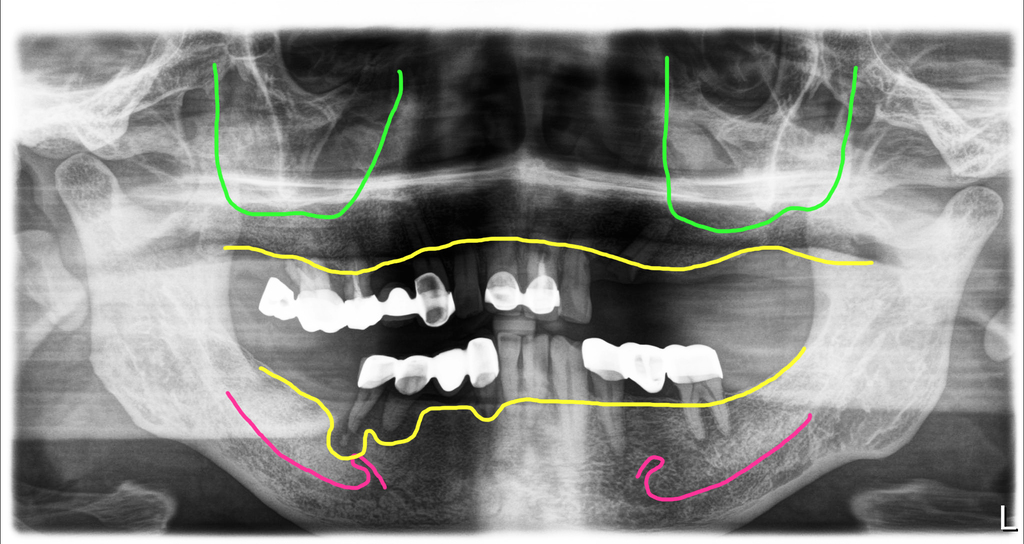

염증이 심한 5번 치아부위에는 임플란트를 심지 않았고 4번은 뼈가 많이 파괴된 것처럼 보이지만 바깥쪽 뼈만 약간 무너져 있어서 혀쪽에 남아있는 뼈에 식립을 해서 전체적으로 뼈이식을 필요하지 않았습니다.

이렇게 식립을 했고 여기에도 수술당일 임시치아를 만들어 드렸어요. 하지만 이런 경우에는 위에 치아와 살짝 닿지 않게 교합을 형성해야 합니다.

이 분의 경우 환자의 요청에 의해 위아래를 나누어서 한달 간격을 두고 수술을 했습니다. 첫번째 수술 후 4개월째, 두번째 수술기준으로 3개월째 치료를 마무리했습니다. 이렇게 이런 환자의 경우 염증이 심한 부위에는 임플란트를 심지 않고 인공치로 연결하는 방식으로 처리해서 뼈이식을 최소화하고 또 하악신경손상을 방지하는 방식이 좋습니다.